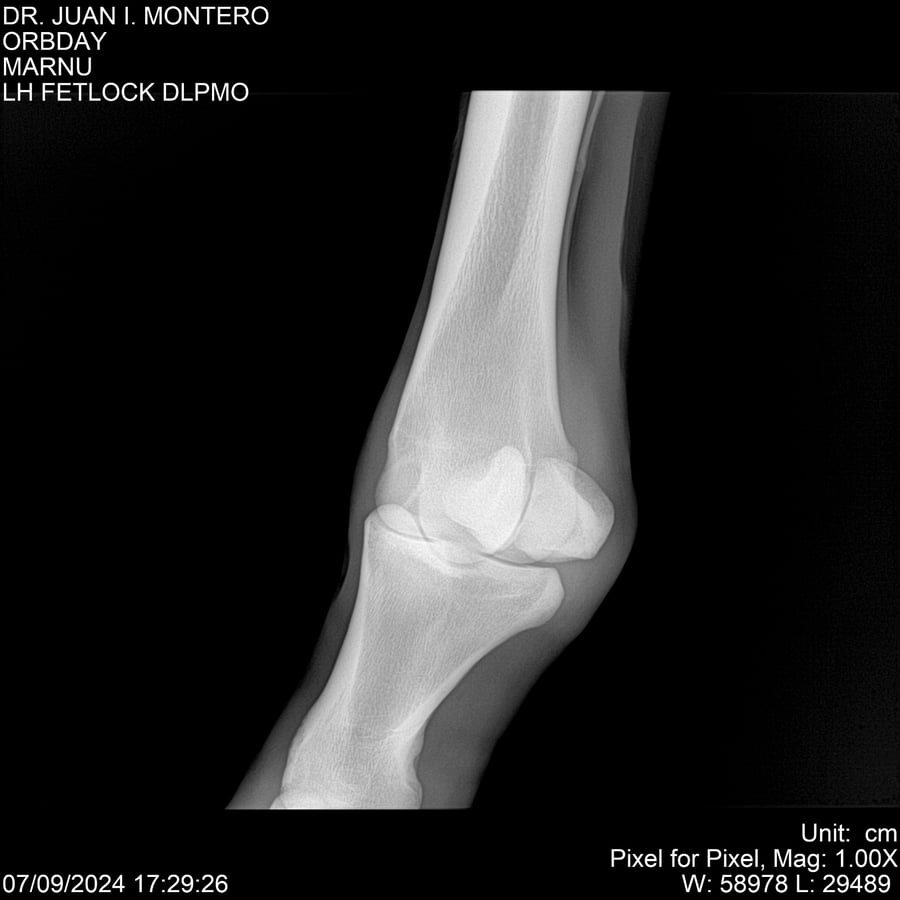

• Empresa: Abelenda N. R., Walter Hugo